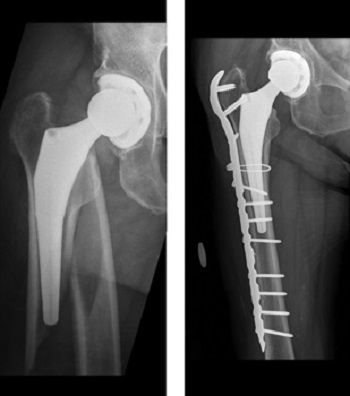

x-ray of periprosthetic hip fracture

(Left) This X-ray taken from the front shows a periprosthetic hip fracture. (Right) The fracture has been treated with a plate, screws, and cable.

Reproduced from Pike J, Davidson D, Garbuz D, et al: Principles of treatment for periprosthetic femoral shaft fractures around well-fixed total hip arthroplasty. J Am Acad Orthop Surg 2009; 17: 677-688.